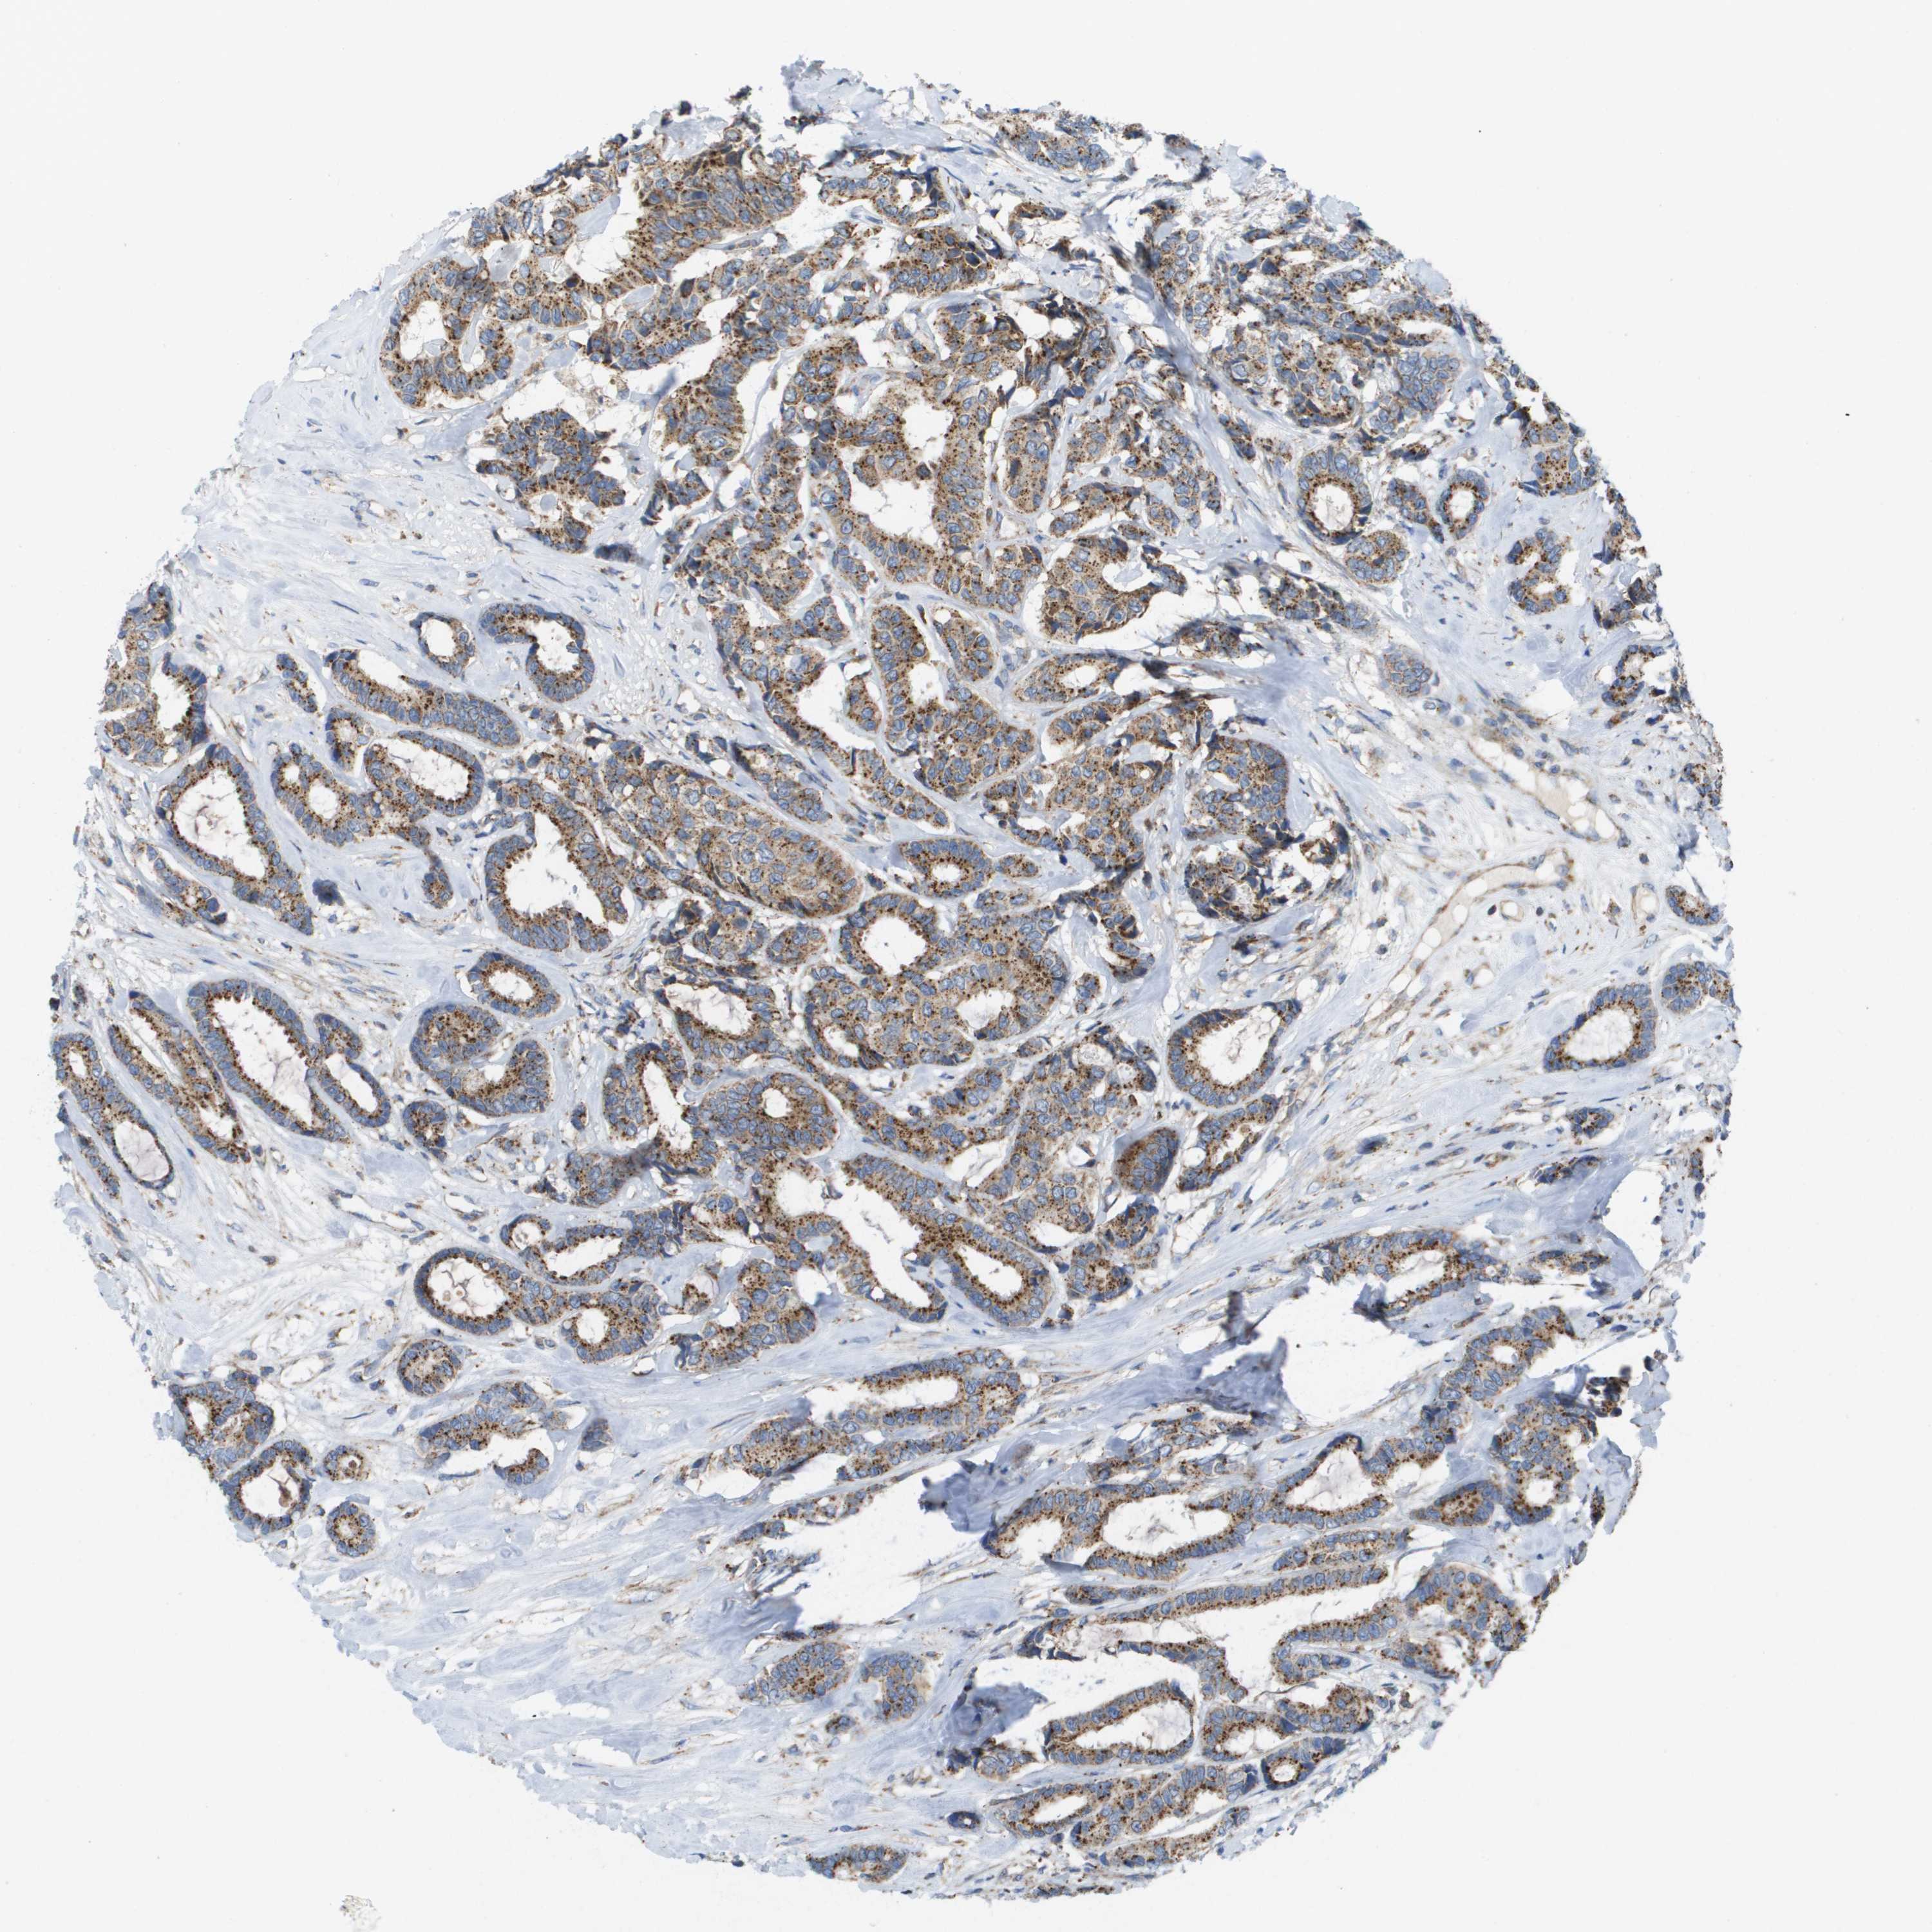

CANCER BREAST CANCER Show tissue menu

BRCA TCGA BRCA VALIDATION PROTEIN EXPRESSION

ANTIBODIES

AND

VALIDATION